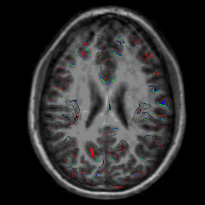

我想在T1.mgz上重新创建一个FreeSurfer pial/白色表面的web版本,类似于freeview上的第一个freeview图像。使用XTK,我可以从Othographic Projection in XTK获得一些提示。我用来创建映像的代码(以及多次尝试生成的kruft )在图像下面。

Green is orig<br>

Red is pial<br>

Blue is white<br>